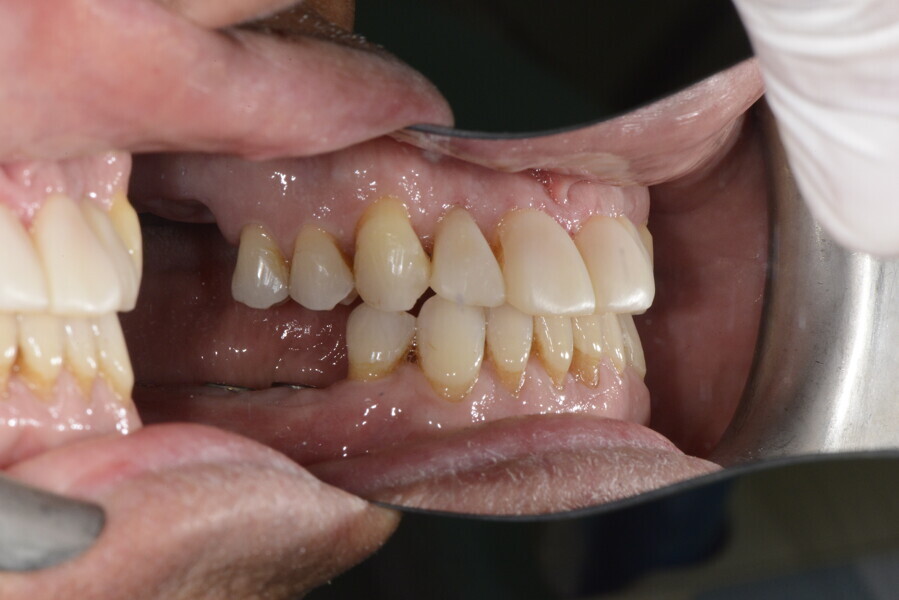

The 58-year-old patient wished to improve his oral aesthetics and function, complaining of mobility of the posterior teeth and wear of the anterior teeth. After data collection, a very complex situation was identified (Figs. 11–13):

1. severe periodontitis with poor prognosis of some teeth;

2. anterior crossbite;

3. severe wear mainly of the anterior teeth and compensatory eruption;38

4. atypical swallowing and lower posture of the tongue at rest;

5. masticatory dysfunction during the mastication test; and

6. no significant signs of temporomandibular disorder.

After the first phase of aligner treatment, we had achieved better inter-arch coherence, better maxillary arch expansion, and some space for improving the anterior tooth proportions restoratively (Fig. 19). We then temporarily restored the anterior teeth directly with composite, closing the spaces, improving the tooth proportions and further increasing the maxillary arch expansion (Fig. 20). We used restorative arch expansion to reduce the orthodontic destabilisation of the teeth to achieve the correct inter-arch coherence and retain the teeth in the cortical bone.38 A refinement aligner phase was undertaken to improve the final alignment of the gingival zenith and to improve the inter-arch coherence (Fig. 21). The periods of the first orthodontic phase and of the refinement were used to augment the mandibular and maxillary bone and to place the implants (Fig. 22). At the end of the orthodontic treatment, the case was finalised with ceramic veneers in the anterior area and temporary restorations on the implants in the posterior area (Figs. 23–26).